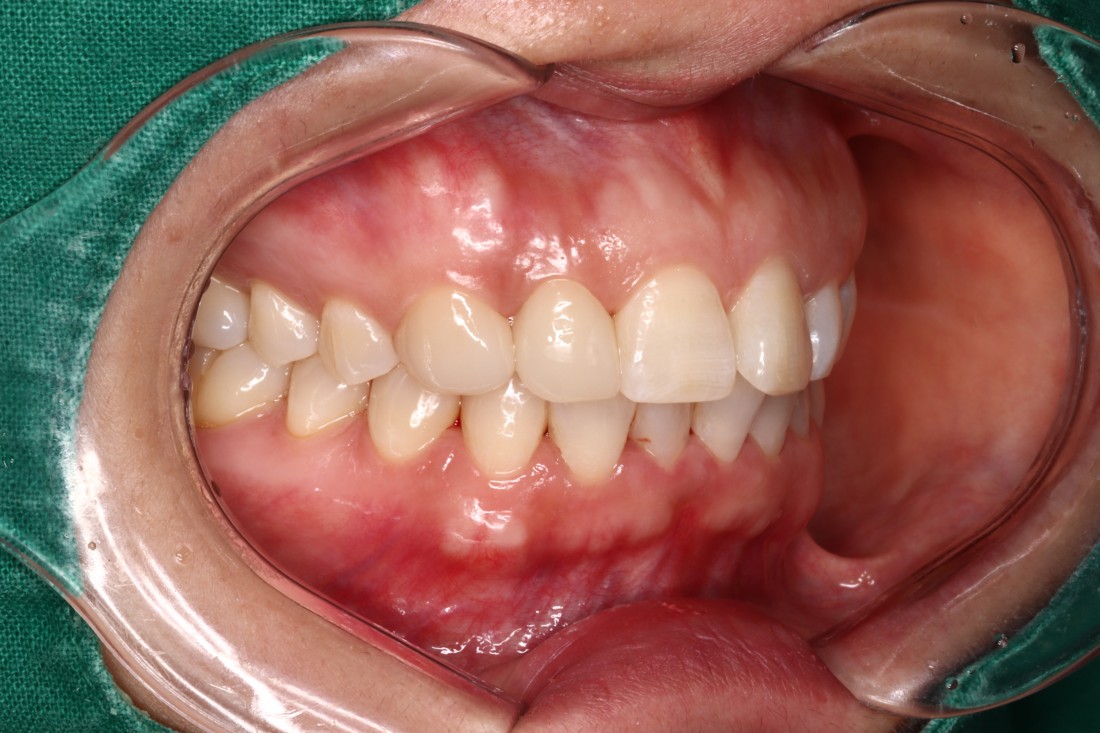

광주 앞니교정 앞니부분교정이나 급속앞니교정을 원할 때는 바로 이 진료를 추천합니다